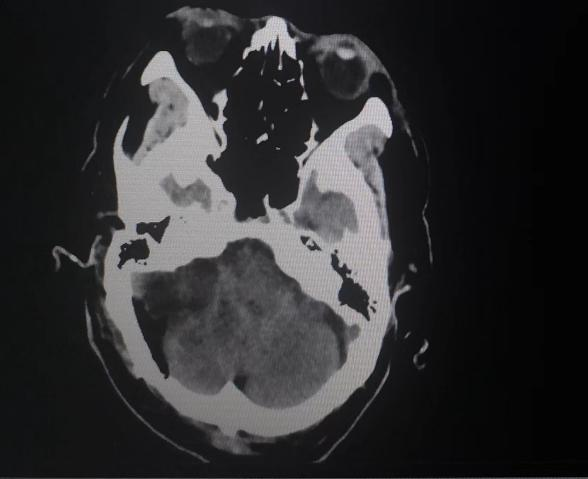

患者入院后,头颅MR检查后发现,小脑右侧长了巨大肿瘤,直径约6公分,患者家属收到不小的惊吓。患者4年前曾做过一次头颅核磁共振,当时肿瘤较小,考虑到患者已经88岁,家人还是决定保守观察,没想到如今,它已经长大到足足有一个土豆那么大,而且患者头晕较重,反复恶心、呕吐,卧床不起,因此必须进行手术,才能解决患者病症。

手术时,在显微镜下沉着应对,先切断肿瘤血液供应控制出血,一边分块切除肿瘤,一边对肿瘤进行精细剥离,仔细保护与肿瘤粘连紧密的重要神经、血管结构,最后在显微镜下全部切除肿瘤,而且完整保留了神经功能,手术取得圆满成功。